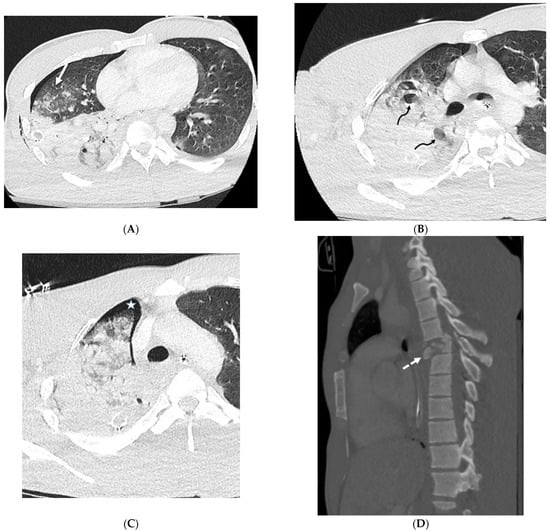

4.1. Lipoid Pneumonia

4.2. Drug-Induced Pneumonitis

4.3. Immunotherapy-Related Side Effects

4.4. Electronic Cigarette or Vaping Use-Associated Lung Injury (EVALI)

4.5. Radiation Pneumonitis

4.6. Silicone Embolization

4.7. Pulmonary Vein Stenosis (PVS)